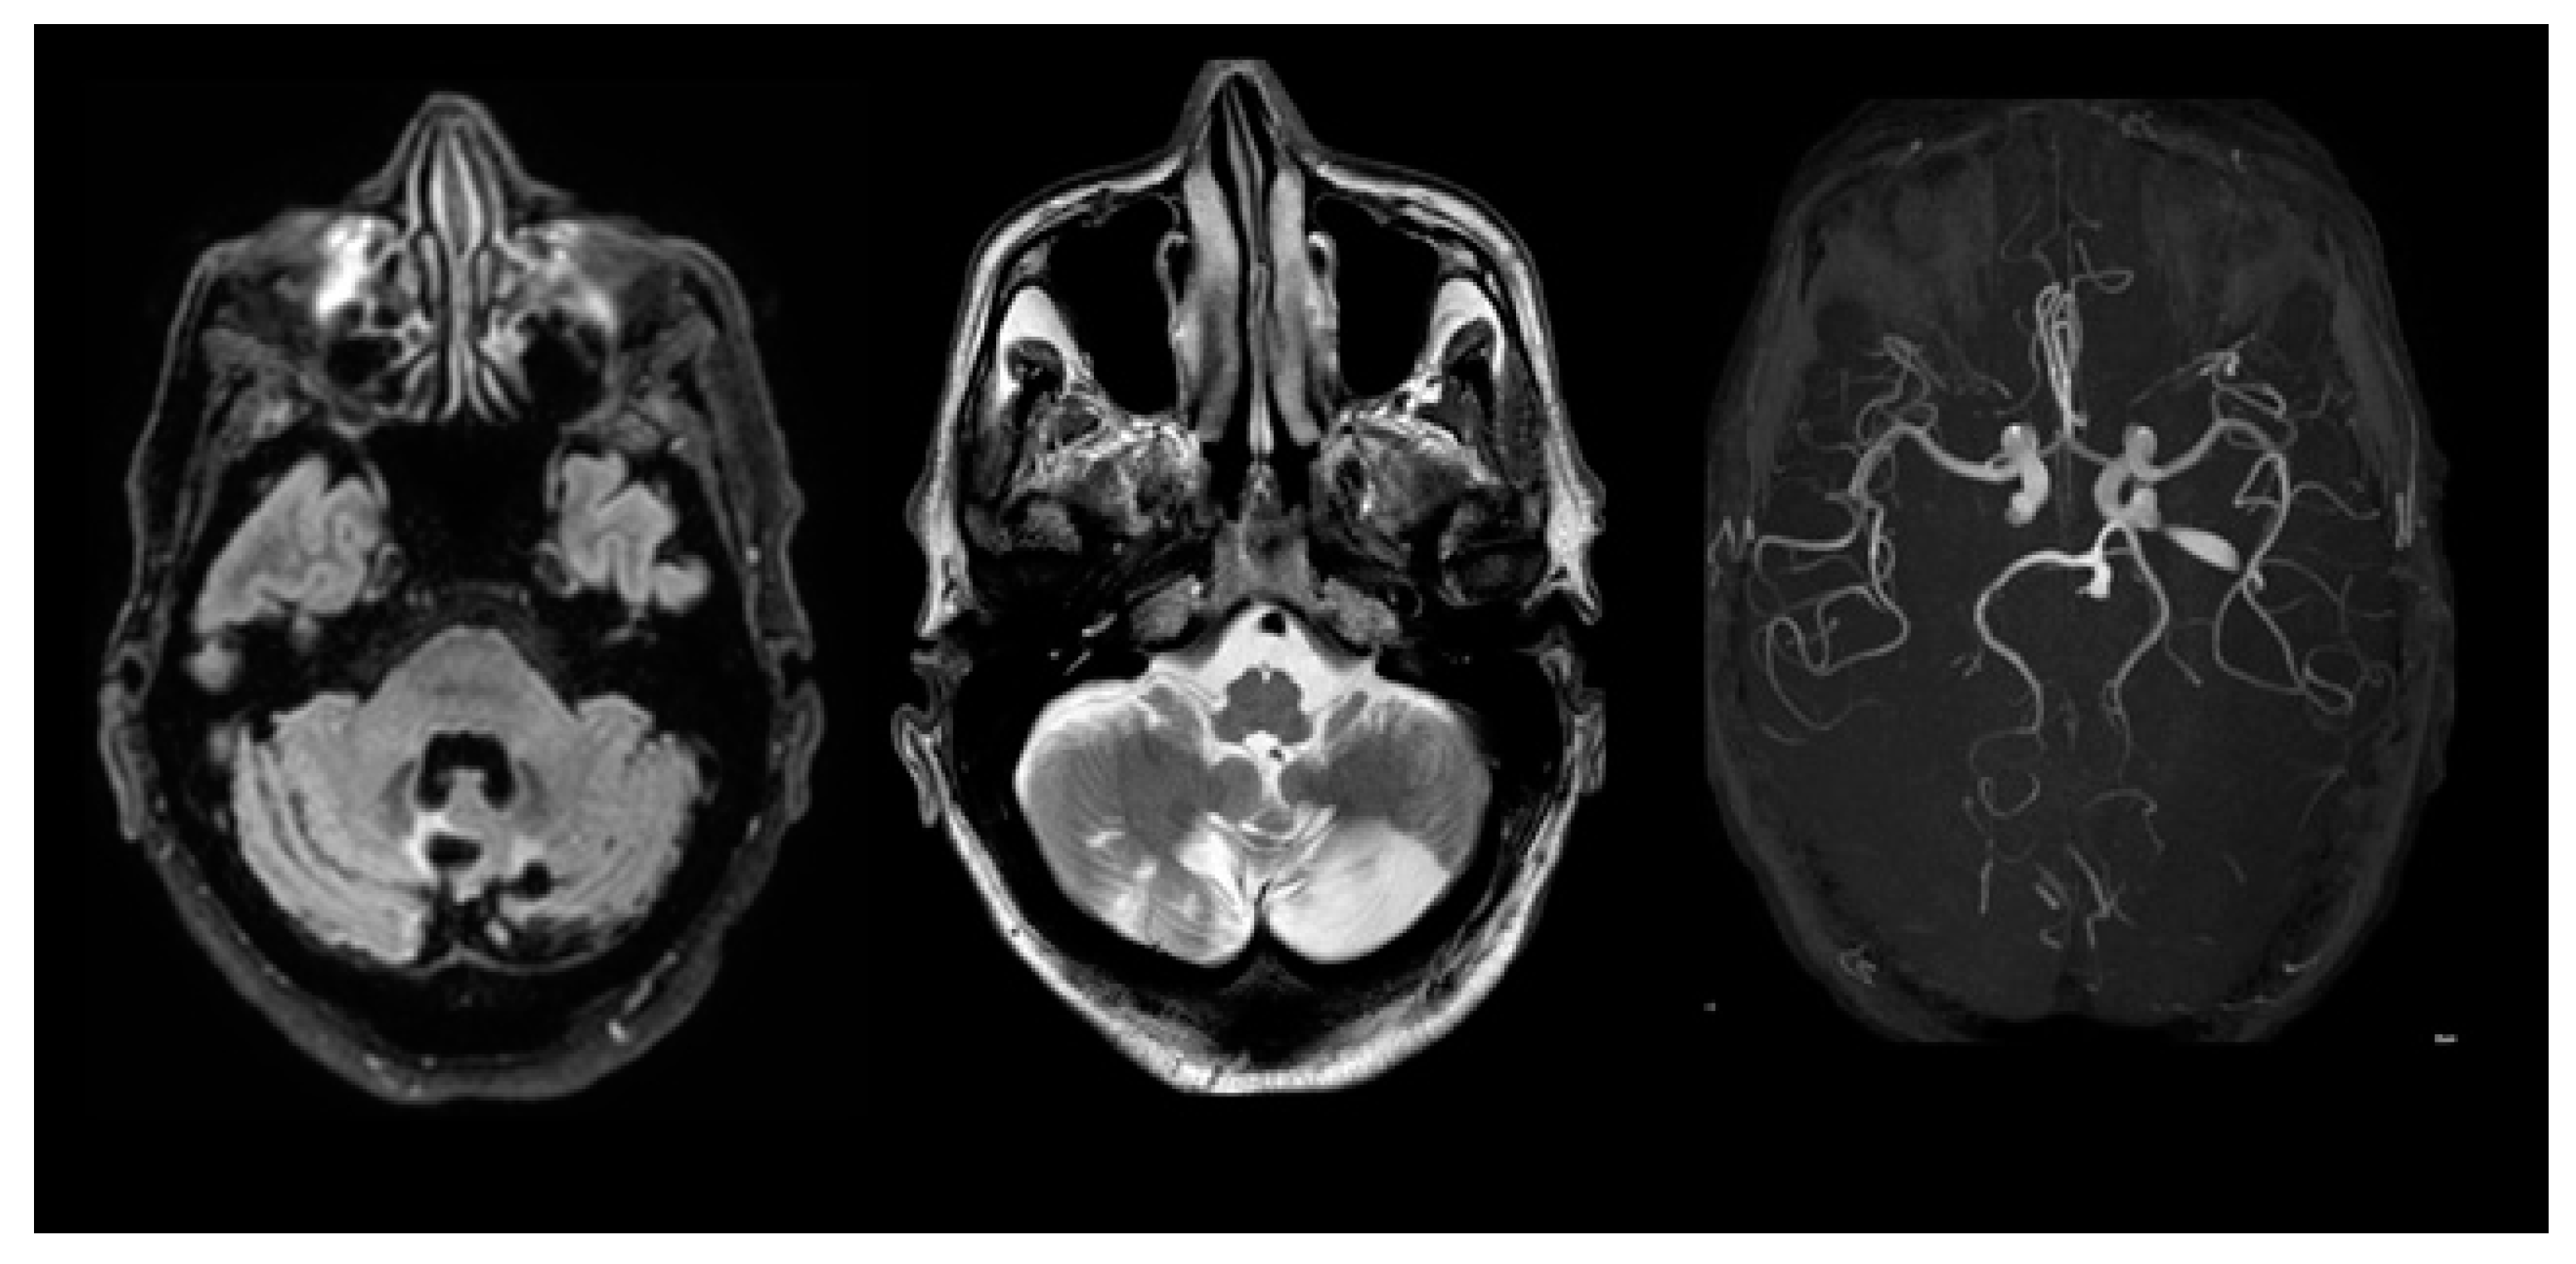

2. Case Presentation